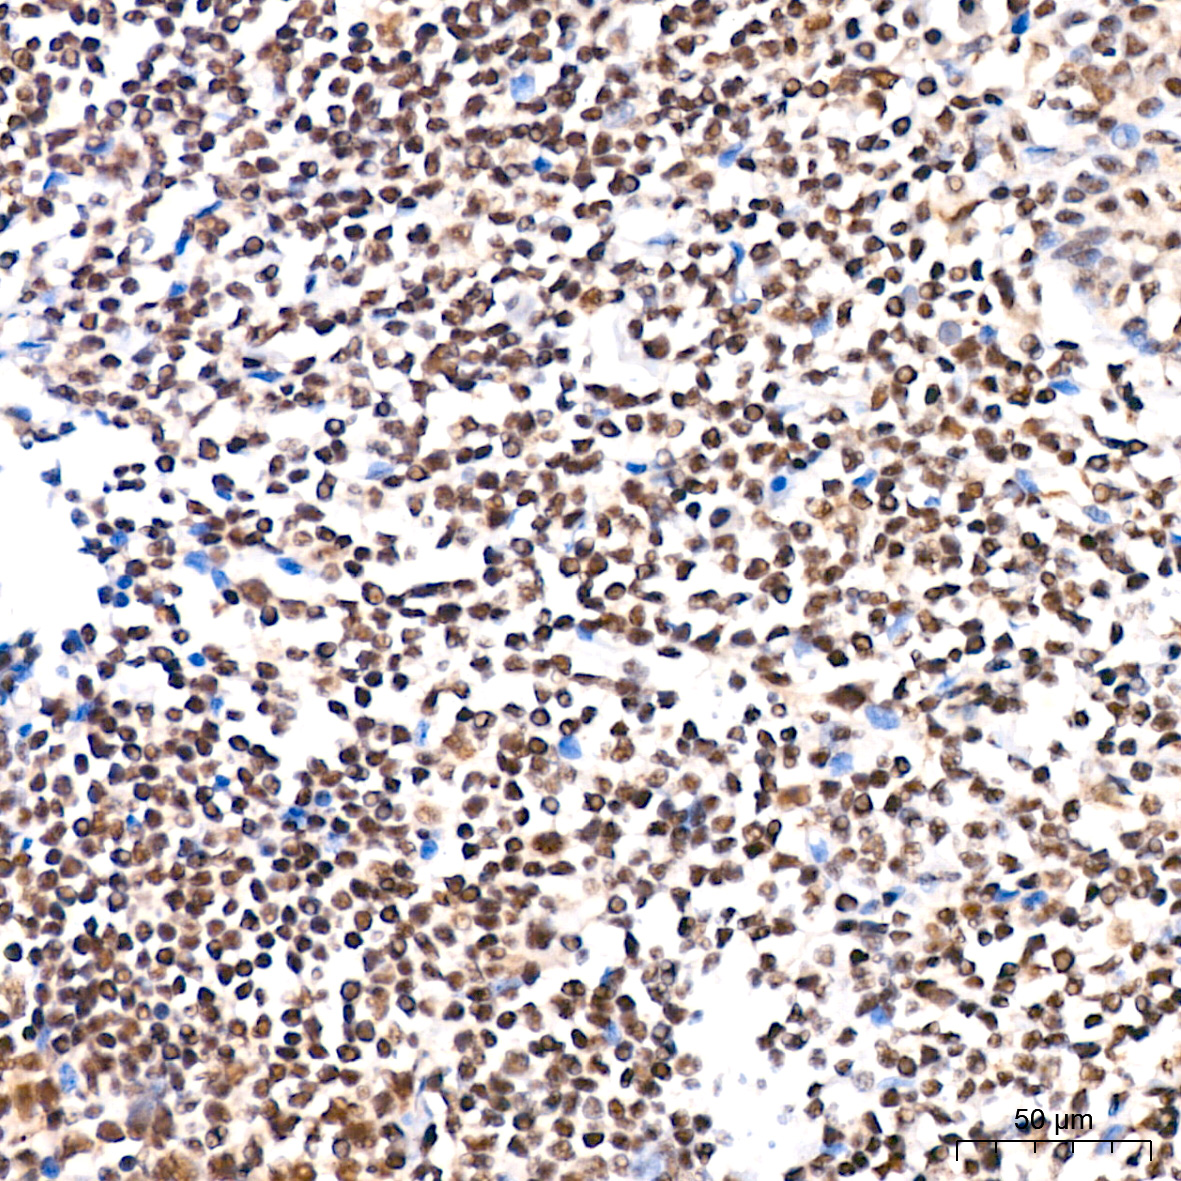

ABclonal基于第四代重组兔单抗SMab®技术平台,以ISO9001和ISO13485质量管理体系标准,为科研工作者研发并生产了一系列高特异性和高稳定性重组单克隆和多克隆抗体产品,这些抗体已针对多种应用进行了全面验证,用于神经谱系、神经退行性疾病(阿尔兹海默症、帕金森氏症、神经炎症)、神经发生、神经营养等神经生物学研究!